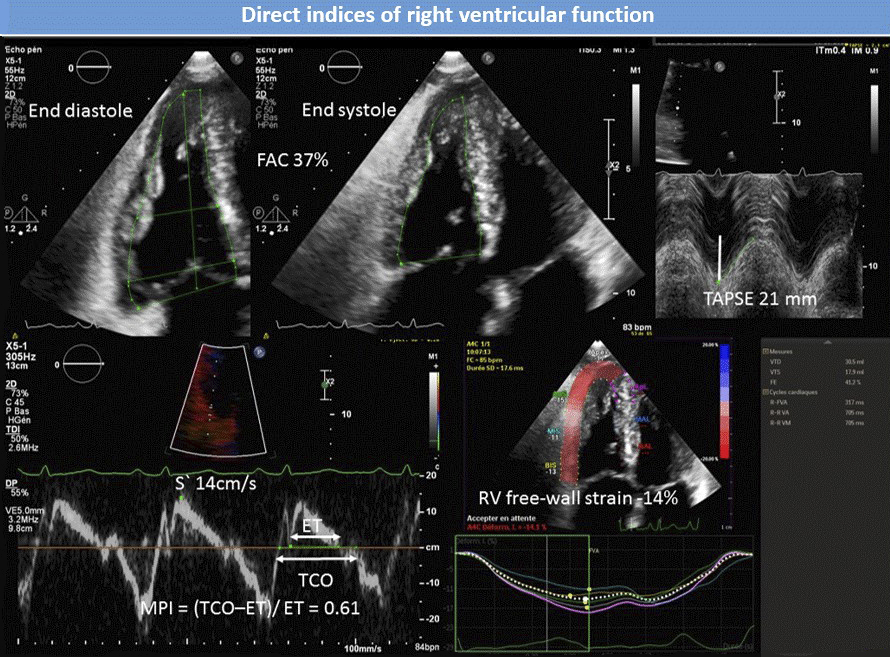

Figure 4 76-year-old male with pulmonary arterial hypertension. Normal TAPSE, S′ velocity and FAC with abnormal MPI and right ventricular free-wall strain. FAC = fractional area change; TAPSE = tricuspid annular plane systolic excursion; S′ = TA tissue Doppler velocity; MPI = Tei index; TCO = tricuspid valve closure to opening time; ET = ejection time.